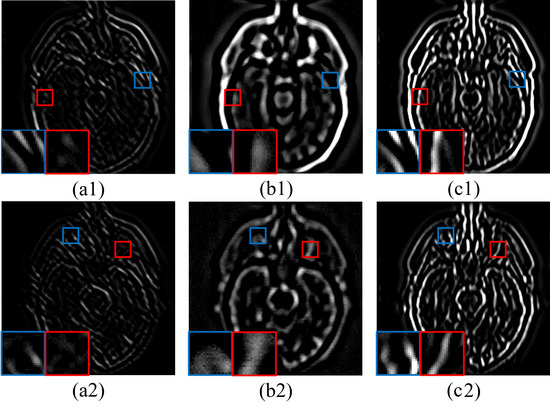

5.2.1. Fusion Analysis on T1-T2

5.2.2. Fusion Analysis on T2-PD